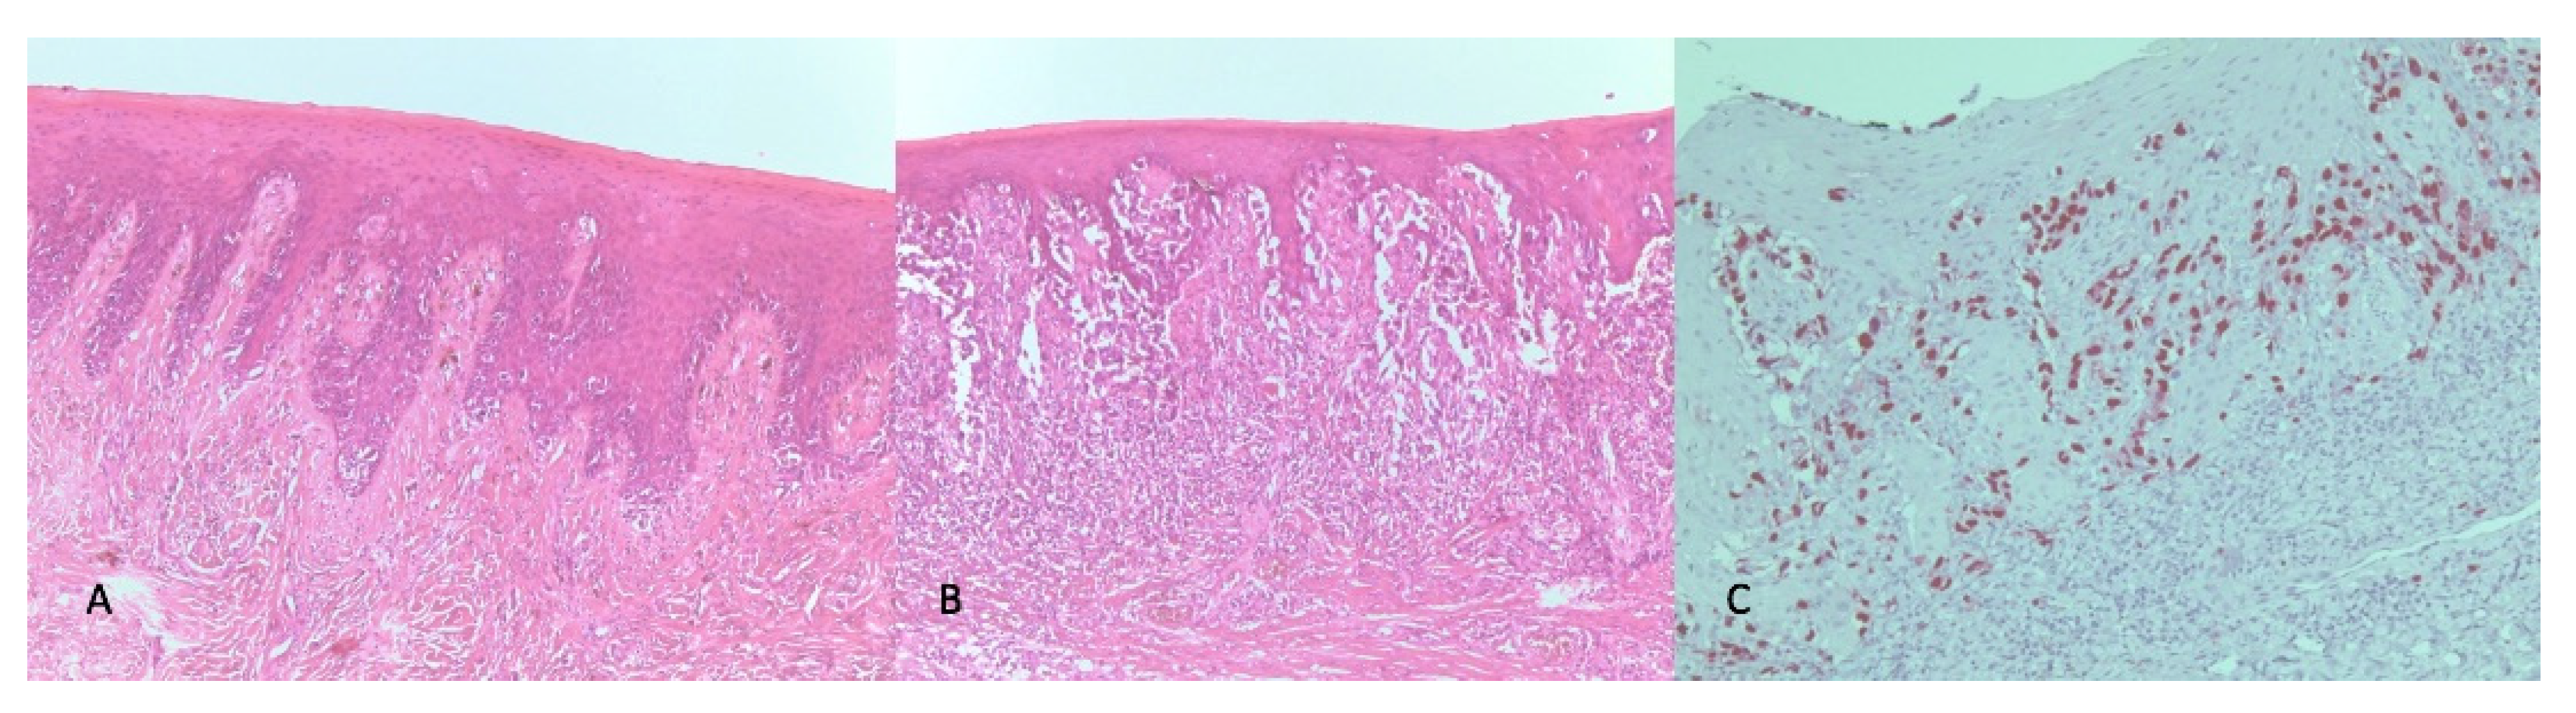

2. Case Report